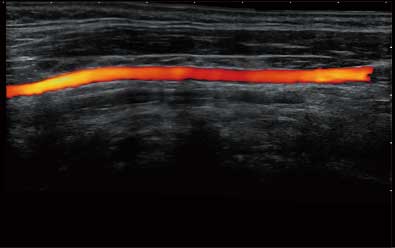

结合开立超宽频带探头技术优势,能够更好地获得高分辨力与高穿透力的平衡,保证图像质量,为临床诊断保驾护航。

微米成像技术提升了对组织斑点噪声信号的抑制能力,并进一步强化边界信息,从而获得清晰图像。